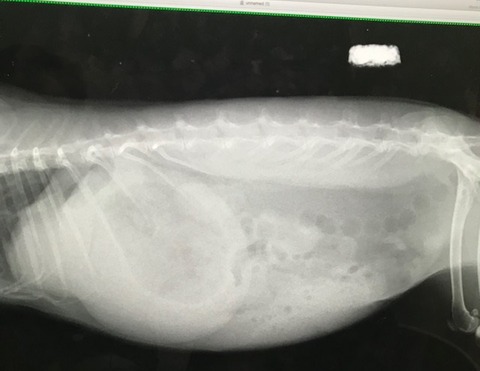

どういう状態か詳細知りたかったのでレントゲンはお願いした。

閉塞所見はないが、閉塞しかけ、とも取れる図。

極度の盲腸うっ滞か、うんこは出番待ち、ガスに少し動きがあるので

自身で頑張って動かし中、というところ。